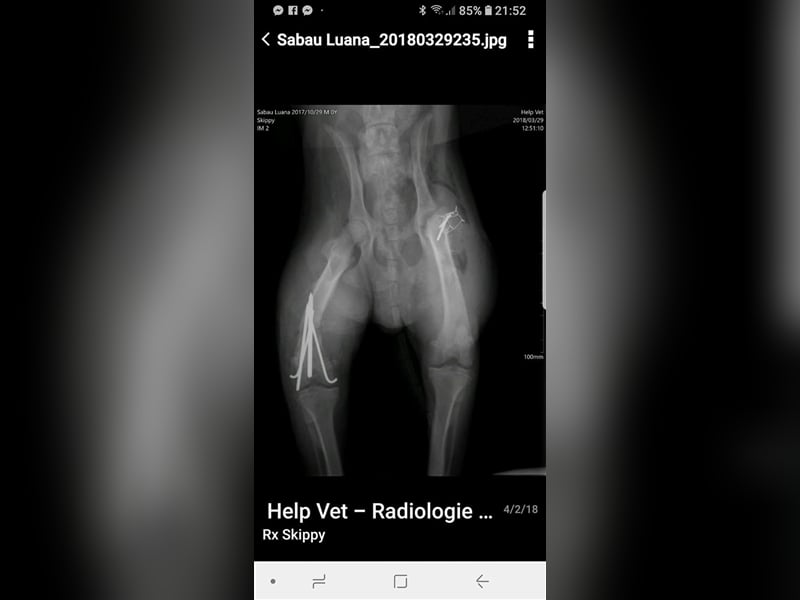

Skipper wurde im Oktober 2017 geboren, hat eine Schulterhöhe von knapp 50 cm und ist kastriert. Der Rüde wurde verletzt im Straßengraben gefunden, beide Hinterbeine waren gebrochen, doch er konnte erfolgreich operiert werden. Er ist inzwischen wieder flott auf seinen vier Beinen unterwegs, auch wenn sein Bewegungsablauf nicht ganz rund ist, so schränkt ihn seine minimale Behinderung nicht ein, fällt auch kaum auf und er ist auf seinen vier Beinen flott unterwegs. Der hübsche Rüde wird vielleicht nicht der ideale Begleiter für längere Joggingrunden oder Radtouren sein, aber nicht jeder Mensch ist ein Sportfreak und Skipper ist auf keinen Fall ein Couchpotato. Skipper lebt seit Juli bei einer Pflegefamilie in Dortmund zusammen mit anderen Hunden und kann dort gerne kennengelernt werden.

Skipper wurde im Oktober 2017 geboren, hat eine Schulterhöhe von knapp 50 cm und ist kastriert. Der Rüde wurde verletzt im Straßengraben gefunden, beide Hinterbeine waren gebrochen, doch er konnte erfolgreich operiert werden. Er ist inzwischen wieder flott auf seinen vier Beinen unterwegs, auch wenn sein Bewegungsablauf nicht ganz rund ist, so schränkt ihn seine minimale Behinderung nicht ein, fällt auch kaum auf und er ist auf seinen vier Beinen flott unterwegs. Der hübsche Rüde wird vielleicht nicht der ideale Begleiter für längere Joggingrunden oder Radtouren sein, aber nicht jeder Mensch ist ein Sportfreak und Skipper ist auf keinen Fall ein Couchpotato. Skipper lebt seit Juli bei einer Pflegefamilie in Dortmund zusammen mit anderen Hunden und kann dort gerne kennengelernt werden.